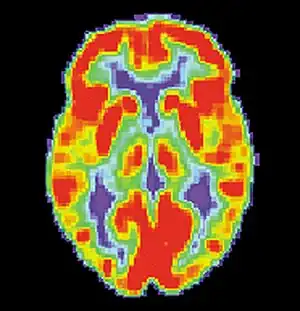

Brain positron emission tomography is a form of positron emission tomography (PET) that is used to measure brain metabolism and the distribution of exogenous radiolabeled chemical agents throughout the brain. PET measures emissions from radioactively labeled metabolically active chemicals that have been injected into the bloodstream. The emission data from brain PET are computer-processed to produce multi-dimensional images of the distribution of the chemicals throughout the brain.[1]: 57